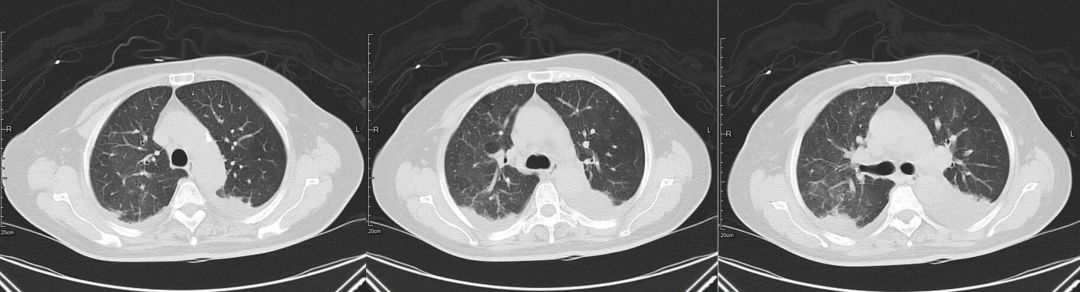

治疗前(2019-03-05)

治疗后(2019-03-08)

胸部CT:两肺多发斑片状渗出影,部分实变,两侧胸腔积液,双下肺膨胀不全,两肺门增大,纵隔内多发淋巴结。

3、辅助检查。胸部CT:双肺多发斑片状渗出性,部分实变,双侧胸腔积液。心超:左心增大伴中度二尖瓣关闭不全、主动脉瓣退行性变伴中度关闭不全、肺动脉高压伴轻中度三尖瓣关闭不全、房间隔膨出瘤(未破裂),EF 60% 正常。

该病例中患者影像学提示双肺多发弥漫性渗出影,没有及时鉴别诊断,笼统诊断为肺部感染性疾病,该影像不是肺部病原菌感染特有的表现,它不是感染的代名词。

肿瘤细胞浸润间质所致,咳嗽、咳大量粘液性泡沫性痰,病理可以明确鉴别。该病例中影像学表现密度相对均匀,与大叶性肺炎相比密度稍低,应用加强利尿3天后肺内磨玻璃影迅速吸收,变化快,肺部感染一般需2周甚至更长时间才能吸收,从影像特点及治疗后的反应上来讲均不支持肺炎。